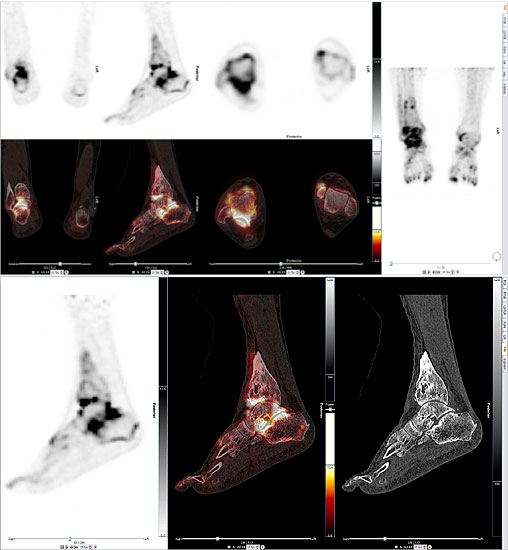

Die Kombination von SPECT und CT in einem Untersuchungsgang bringt wie bereits oben erwähnt eine erhöhte Ortsauflösung und artefaktfreie Darstellung von Knochenstoffwechselveränderungen der SPECT bei gleichzeitig excellent guter anatomischer Darstellung/Zuordnung durch die CT 3. Auf die Vorteile der CT gegenüber dem konventionellen Röntgen muss nicht mehr besonders eingegangen werden. Besonders eignet sich die „SPECT-CT“ zur Diagnostik von Fußerkrankungen (Biersack HJ et al. 2012).

Aufgrund der optimalen funktionellen Darstellung (PET) und der entsprechend guten anatomischen Bildgebung kann dieses kombinierte Untersuchungsverfahren viele Fragestellungen auch im Bereich des Fußes beantworten. Exemplarisch werden folgende Indikationen erwähnt. Abklärung von Infektionen im muskuloskelettalen Bereich 45, Untersuchungen von unklaren Fußschmerzen (Biersack HJ et al. 2012), präoperative Bildgebung beim Charcot-Fuß/diabetischer Fuß 31.